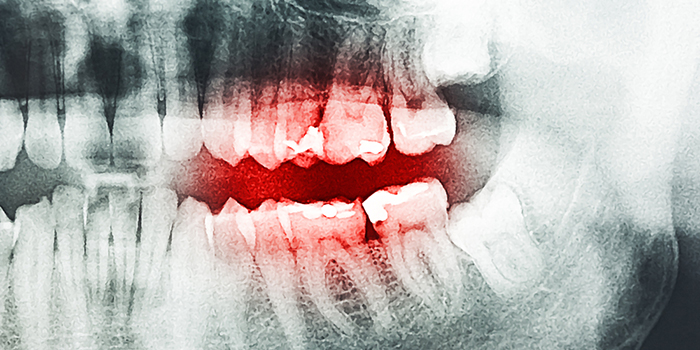

■ 虫歯の進行順

1. 歯のエナメル質

2. 歯肉及び神経

3. 骨

4. 全身へ

虫歯の進行段階は歯のエナメル質、歯肉及び神経、骨へと続き、全身へと血管を通して原因菌が運ばれます。

この段階に至ると各種の重篤なリスクを覚悟しなければなりません。